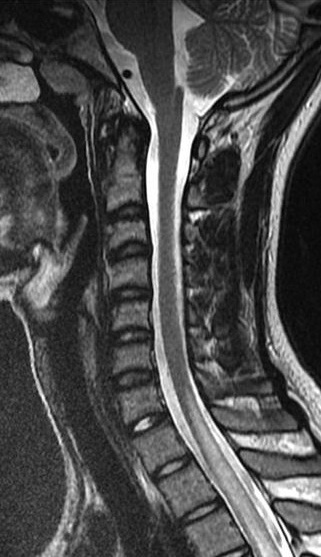

A MRI scan of brain and spine showed increased T2 signal and expansion of the cord in some areas of the spinal cord at the levels of C2–C5, and C7 to T12. The patient was given methylprednisolone 1 gram intravenous for a period of 5 days and oral steroids for 4 weeks. Thyroid function tests were reported to be normal (Table 3 [Tab. 3]). The patient showed marginal improvement in vision and reduction of sensory abnormalities by about 50% over a period of 6 weeks. In April 2015, the patient was admitted with cough associated with mucopurulent expectoration, shortness of breath, paraesthesias and diminished vision. The patient showed minimal improvement in sensory symptoms or vision. In May 2015, the patient was admitted with progression of bilateral lower limb weakness, bilateral upper limb weakness (distal > proximal) and a band-like sensation around the chest, syncope, vomiting and hiccups. Clinical examination revealed normal higher mental functions with diminished vision to finger counting in the right eye. Other cranial nerves were normal.

Immunological tests for ANA titer were 1:320, tests for anti-ENA, anti-dsDNA, anti-cardiolipin, anti-β2GPI, lupus cells, antibodies to GAD65, IA-2, insulin and cryoglobulins were negative. MRI brain and whole spine revealed 1) hyperintensity in cervical cord C5 to C7 level (Figure 1 [Fig. 1], Figure 2 [Fig. 2], Figure 3 [Fig. 3]); 2) hyperintensity in the thoracic cord till T12 level (Figure 4 [Fig. 4], Figure 5 [Fig. 5], Figure 6 [Fig. 6]); 3) hyperintensity in the right optic nerve head (Figure 7 [Fig. 7]). The clinical features and investigations (NMO IgG was positive) fit into the criteria of neuromyelitis optica. The thyroid profile was suggestive of hypothyroidism (Table 3 [Tab. 3]). Laboratory studies confirmed the presence of antithyroid antibodies (Table 4 [Tab. 4]). Fine needle aspiration of the thyroid showed lymphocytic infiltration of the thyroid gland (Figure 8 [Fig. 8], Figure 9 [Fig. 9]). The patient was treated with prednisolone 1 g/day for 5 days and azathioprine (2.5–3 mg/kg/daily). The patient showed improvement in motor symptoms and sensory symptoms approximately by 60% after a period of 2 months of treatment. Patient was started on thyroxine 50 μg and later dosage was increased to 100 μg.

Figure 3: MRI spine showing hyperintensity in cervical cord C5 to C7 level (3)